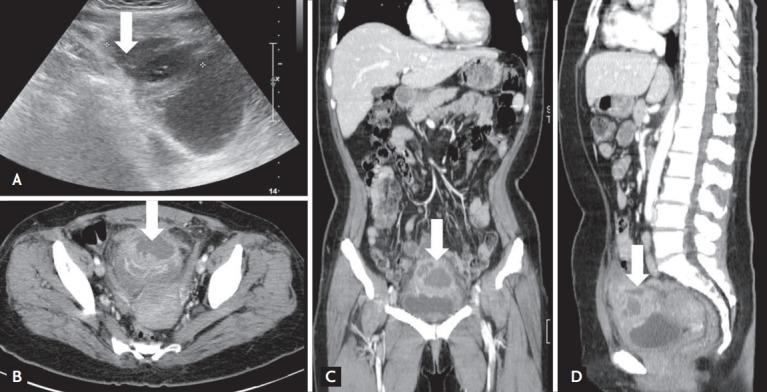

Urachal abscess precipitated as acute pyelonephritis in an adult patient with diabetes.